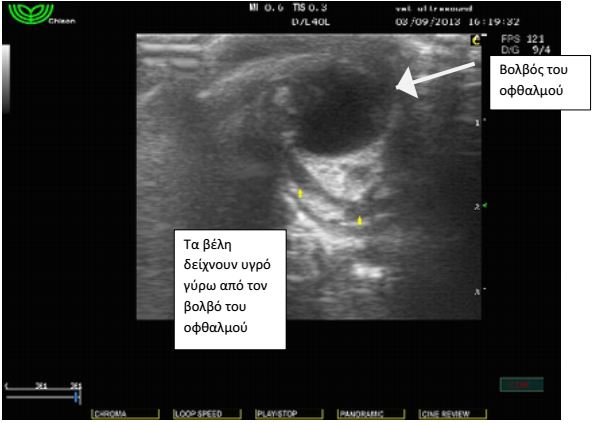

Ασθενής: Γάτα θηλυκή, 2 μηνών, φυλής κοινής ευρωπαϊκής

Προσκομίστηκε με επώδυνη διόγκωση της δεξιάς περιοφθαλμικής

Έγινε υπέρηχος όπου διαπιστώθηκε συγκέντρωση υγρού

αυξημένης ηχογένειας στη περιοχή πίσω από το δεξιό οφθαλμό,

εικόνα συμβατή με οπισθοβολβικό απόστημα. Η αλλοίωση

υποχώρησε τις επόμενες μέρες με αντιβιοθεραπεία και δε

χρειάστηκε να γίνει παρακέντηση.